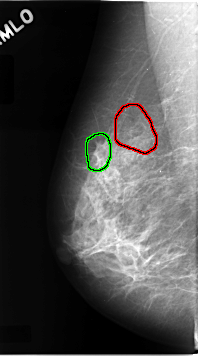

C_0068_1.RIGHT_CC

FILE: C_0068_1.RIGHT_CC.OVERLAY

TOTAL_ABNORMALITIES 2

ABNORMALITY 1

LESION_TYPE CALCIFICATION TYPE AMORPHOUS DISTRIBUTION CLUSTERED

ASSESSMENT 5

SUBTLETY 4

PATHOLOGY MALIGNANT

TOTAL_OUTLINES 1

BOUNDARY

ABNORMALITY 2

LESION_TYPE MASS SHAPE ARCHITECTURAL_DISTORTION MARGINS SPICULATED

ASSESSMENT 4

SUBTLETY 2